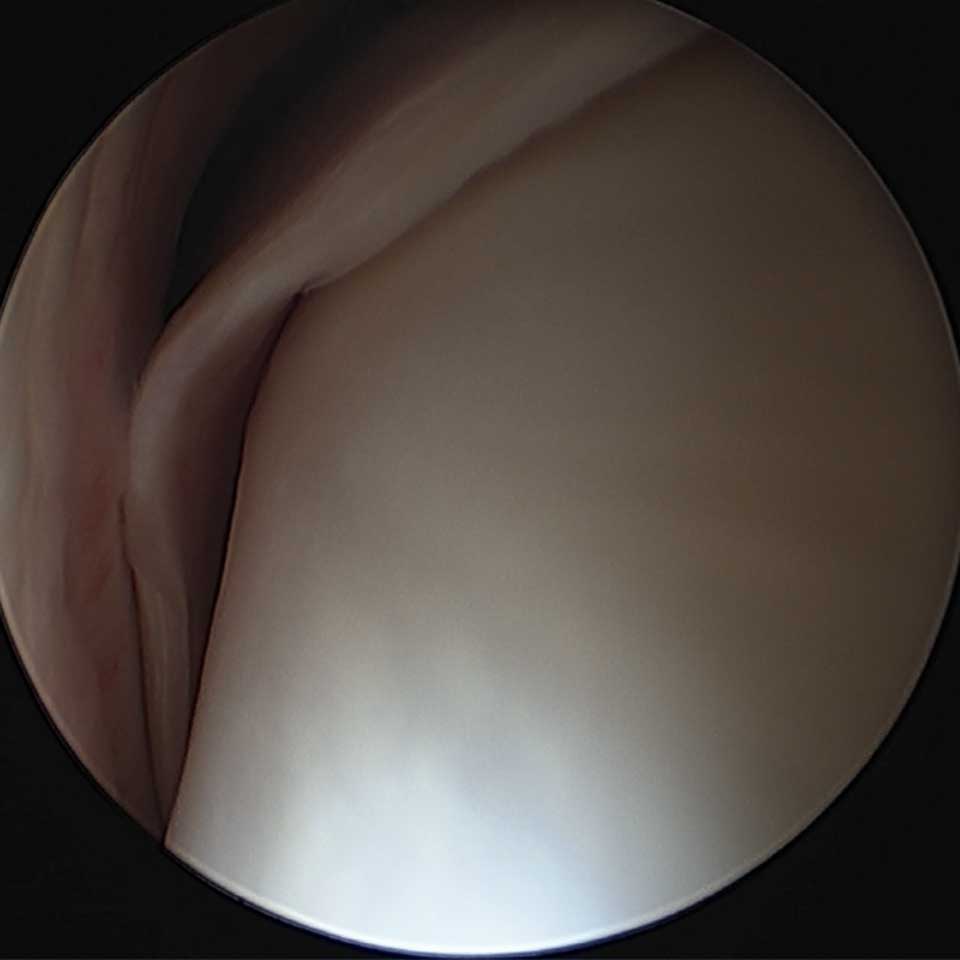

Die Tenoskopie ist eine minimalinvasive Spiegelung der Sehnenscheide, vergleichbar mit einer Arthroskopie im Gelenk. Dabei wird mittels eines kleinen Hautschnitts eine winzige Kamera – das Arthroskop – in die betroffene Sehnenscheide eingeführt. Über einen Monitor kann der Tierarzt die inneren Strukturen der Sehnenscheide direkt beurteilen und je nach Befund gezielt behandeln.

Über kleine Hautschnitte wird das Arthroskop in die Sehnenscheide eingeführt. Je nach Befund werden zusätzliche Schnitte gesetzt, um Operationsinstrumente einzubringen. Die gesamte Operation erfolgt unter Sichtkontrolle am Monitor, sodass gezielt und schonend gearbeitet werden kann.

Verwendet wird ein moderner Arthroskopie-Turm, der eine präzise Darstellung auch feinster Strukturen ermöglicht.